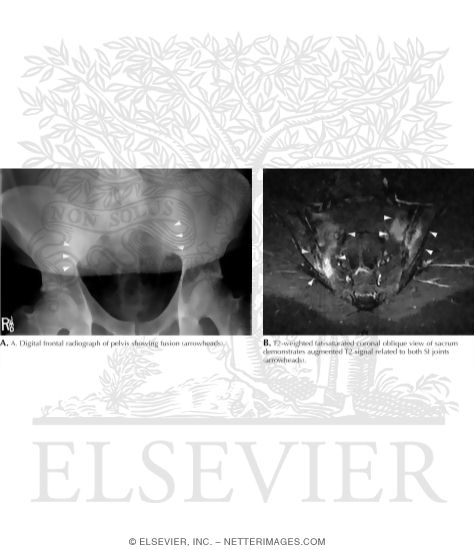

Fusion of Sacroiliac Joints In 28-Year-Old Man With Ankylosing Spondylitis